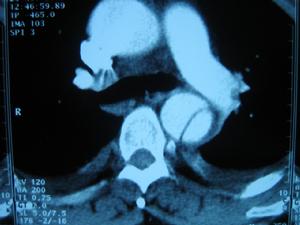

輔助檢查

張平胸部X線檢查:胸部X線檢查是簡便可靠的診斷方法。夾層主動脈動脈瘤累及升主動脈的病例,在胸部X線平片上顯示縱隔陰影向右側增寬,累及降主動脈者則向左側增寬。主動脈弓呈局限性隆起,升主動脈與降主動脈外徑懸殊,升主動脈與主動脈弓擴大、變形。主動脈壁增厚,致內膜鈣化斑與主動脈外緣間距增寬。間隔半小時重複攝片,顯示胸主動脈與縱隔形態發生改變。有時主動脈呈現雙腔陰影。有的病例可顯示胸膜腔積液。胸部X線檢查顯示上述異常者應立即作主動脈造影檢查,要求充分顯示主動脈全長(從主動脈瓣到腹主動脈分叉處)。主動脈造影可顯示主動脈壁剝離形成的血流異常通道壓迫主動脈腔,了解主動脈壁剝離段的長度、內膜裂破的部位、主動脈瓣的解剖及功能情況以及主動脈主要分支如頸總動脈、腎動脈受累情況等。夾層動脈瘤的主動脈造影陽性徵象有:造影劑在主動脈內分為兩個通道且形態不光整,造影劑未能進入主動脈主要分支以及主動脈瓣關閉不全。